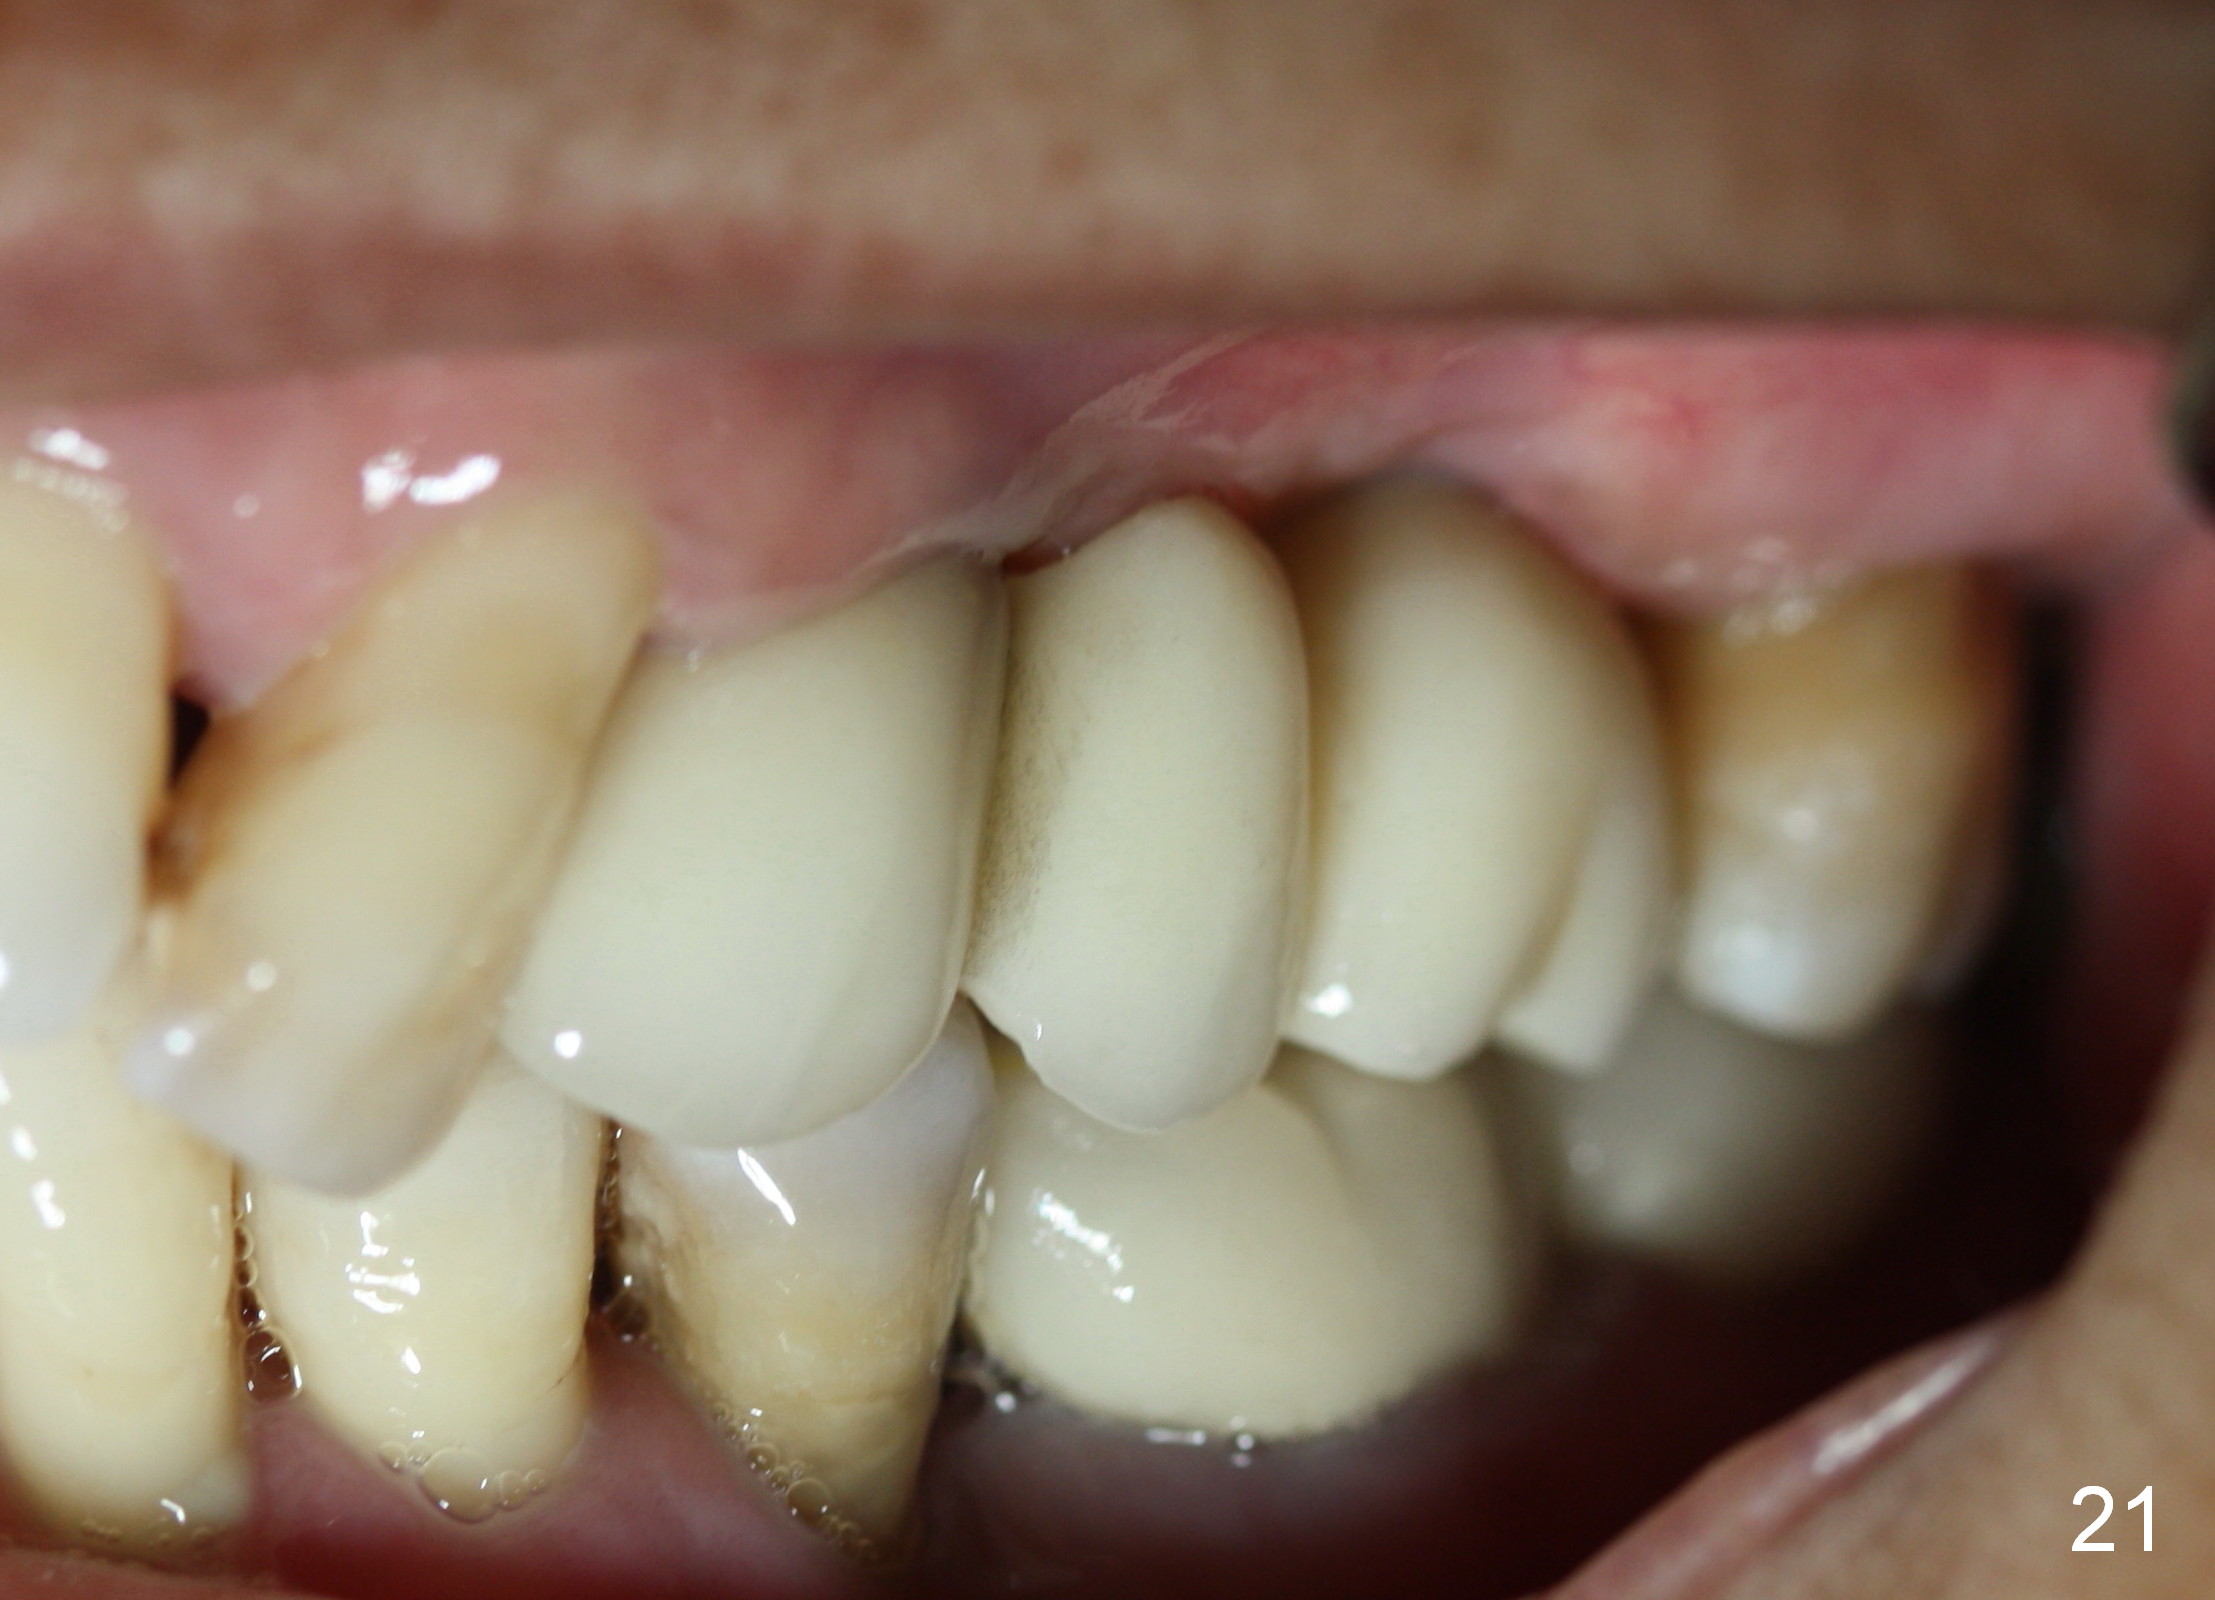

Two PAs are taken 5 months postop (Fig.15,16). Patterns of bone graft (*) between these PAs are different, which suggests presence of the graft buccal to the implant at the site of #14. Another piece of evidence of the graft is that the buccal socket heals (Fig.17 B) without implant thread exposure (Fig.19). These two implants are ready for definitive restoration (Fig.18-20). Fig.21 shows the final restoration 5 months post cementation.